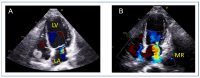

Mitral regurgitation (MR) is a common valvular heart disease associated with significant morbidity and mortality. For patients at high or prohibitive surgical risk, mitral transcatheter edge-to-edge repair (M-TEER) offers a less invasive alternative to surgery. This review outlines key aspects of patient selection and procedural planning for M-TEER, with a focus on clinical and echocardiographic criteria essential for success. Comprehensive imaging-especially 2D and 3D transesophageal echocardiography-is critical to assess leaflet anatomy, coaptation geometry, and mitral valve area. Selection criteria differ between primary and secondary MR and are guided by trials such as COAPT and MITRA-FR. Optimal outcomes rely on careful screening, anatomical suitability, and multidisciplinary evaluation. With growing experience and advancing technology, M-TEER has become a transformative option for treating severe MR in non-surgical candidates.